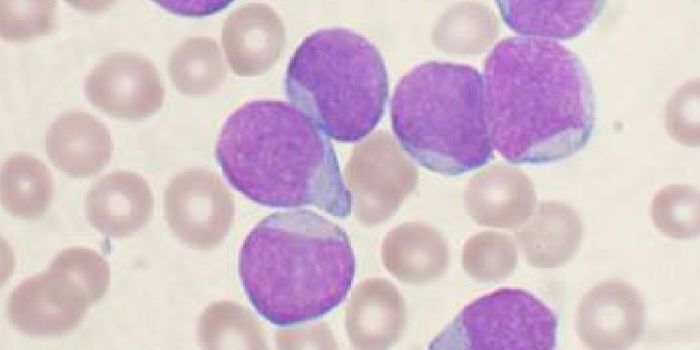

AUG 31, 2017CancerFor patients battling leukemia, there is hope in the form of a newly approved gene therapy. Called Kymriah, this is the ...